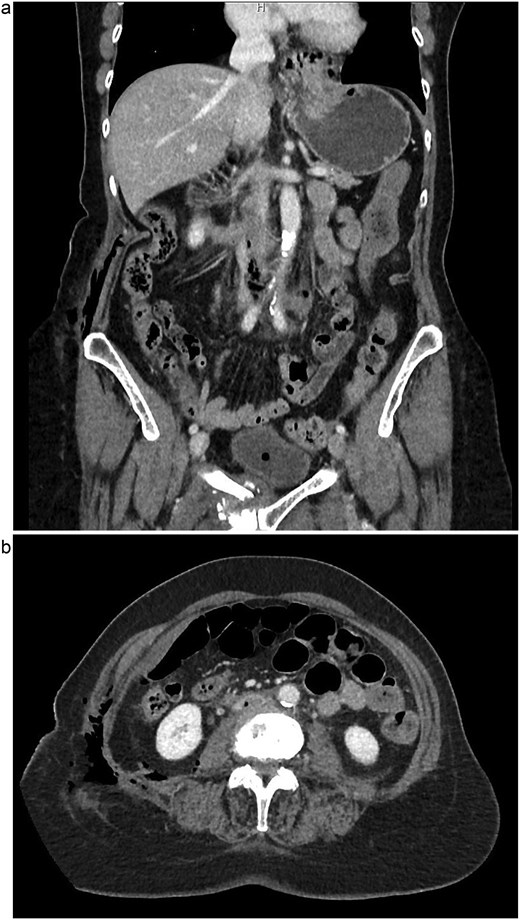

The patient is a 75-year-old female with no relevant past medical or surgical history who underwent an L4-L5 extreme lateral interbody fusion (XLIF) at an outside surgical center. During the procedure, a significant amount of blood loss from an undetermined bleeding vessel was encountered. The primary surgeon injected Surgiflo and Gelfoam to attempt to obtain hemostasis. The XLIF was completed with an estimated blood loss of greater than 2 l. In the post-anesthesia care unit (PACU), the patient remained hypotensive. Two units of packed red blood cells, phenylephrine, 5 l of crystalloid, and 50 g of albumin were administered in the PACU and the patient was transferred to a surgical intensive care unit at a level one trauma center. A computed tomography (CT) scan was obtained which demonstrated a thrombus present in the inferior vena cava (IVC) extending to the left common iliac vein (Fig. 1a and b). She received an additional unit of packed red blood cells and blood pressure support was maintained with norepinephrine. Vascular surgery was consulted. At the time of evaluation, the patient had remarkably improved hemodynamics and was on minimal pressor support. After discussion of risks and benefits of intervention versus medical management, the vascular team recommended therapeutic anticoagulation with continuous intravenous heparin. The patient was observed in the intensive care unit for 2 days until she was off pressor support. She was started on apixaban once her hemoglobin was stable on three consecutive blood draws. A repeat CT angiogram 1 month after discharge demonstrated near resolution with a small residual thrombus in the left common iliac vein (Fig. 2a and b). She has returned to normal activity and will remain on apixaban for 6 months after the inciting event and the thrombus will be evaluated again for further evolution.

(a) Coronal view of resolved thrombus, 5 months post-op. (b) Axial view of resolved thrombus, 5 months post-op.